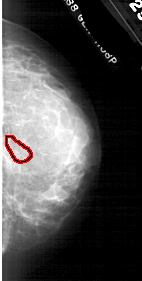

FILE: A_1746_1.RIGHT_CC.OVERLAY

TOTAL_ABNORMALITIES 1

ABNORMALITY 1

LESION_TYPE CALCIFICATION TYPE PLEOMORPHIC DISTRIBUTION CLUSTERED

ASSESSMENT 4

SUBTLETY 1

PATHOLOGY BENIGN

TOTAL_OUTLINES 1

BOUNDARY